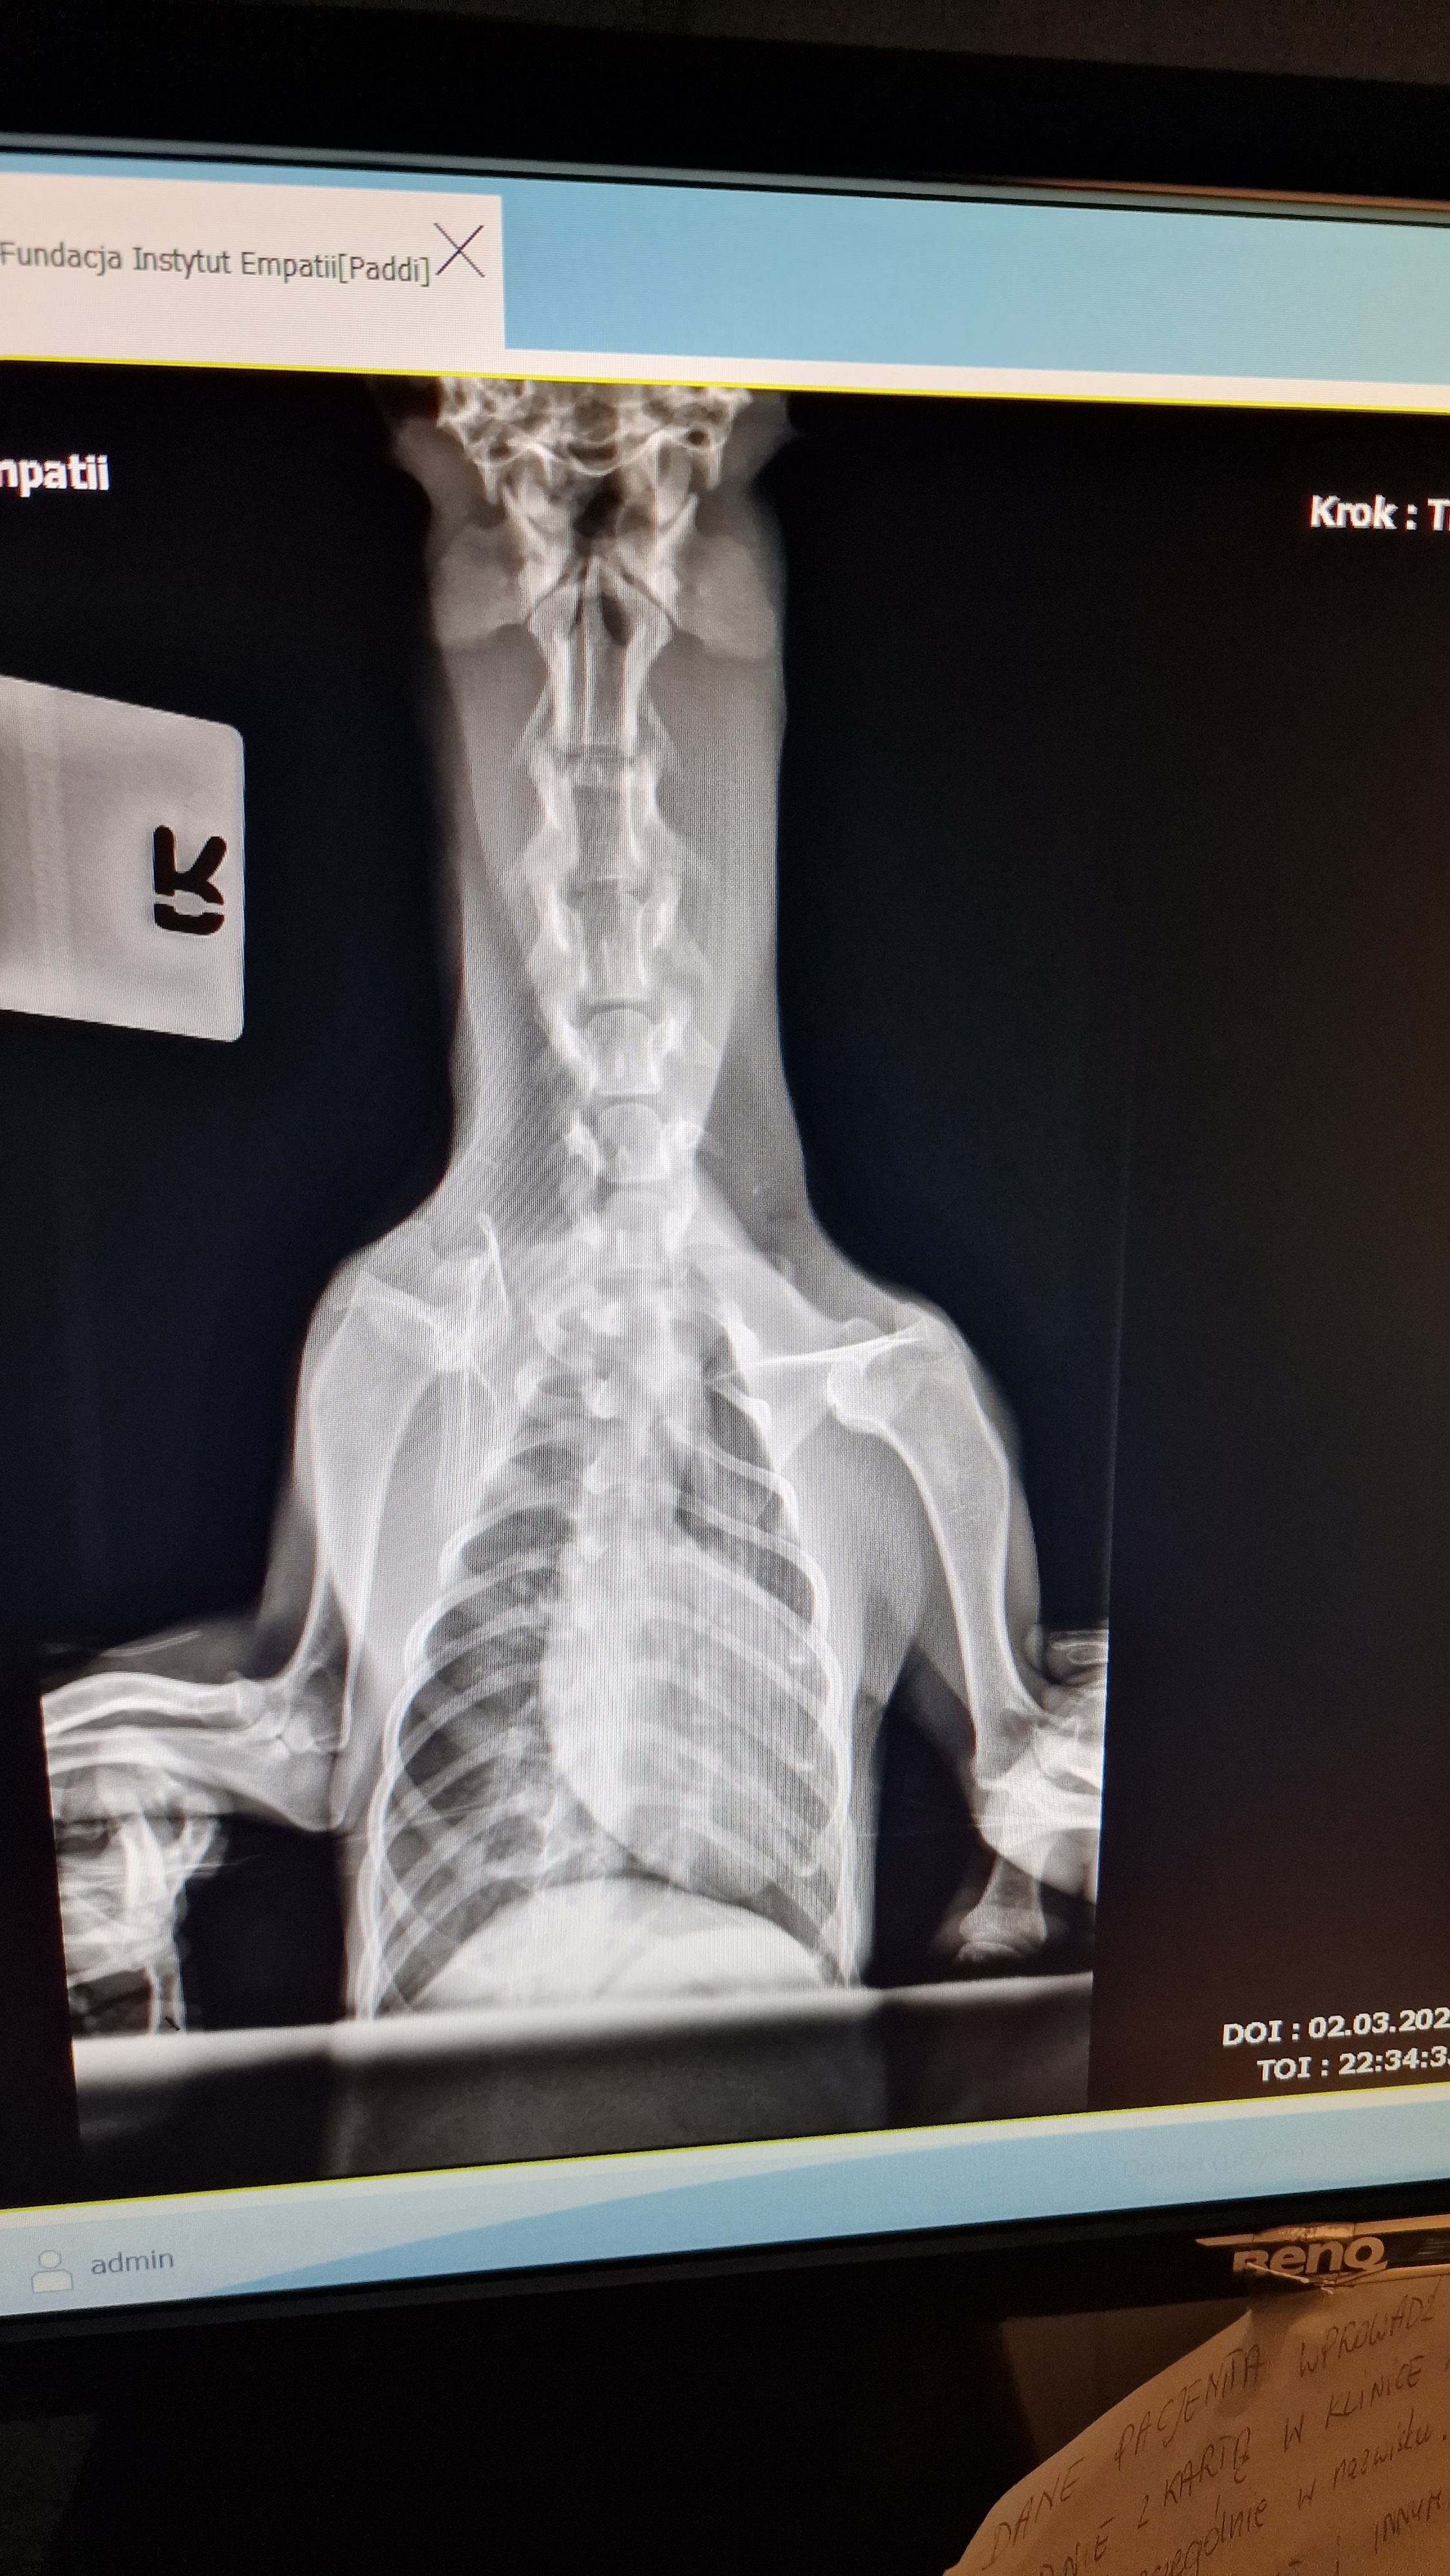

„Przez kilka dni po pobiciu psu nie udzielili pomocy urzędnicy, rodzina, sąsiedzi. Nikt. Obdukcja wykazała liczne obrzęki tkanek miękkich, krwiak na oku, rany kłute i szarpane. Parametry krwi wskazują na obitą wątrobę i trzustkę. Sunia była pod obserwacją neurologiczną ze względu na urazy głowy. Dwie pierwsze noce przebywała na tlenoterapii ze względu na duszność spowodowaną odmą płuc i obrzękiem krtani” - informuje Olga Banach, technik weterynarii.